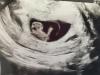

Ja dziś byłam na 3 USG. To 8+4, bąbelek ma prawie 2 cm. Rusza rączkami. Trudno mu było zdjęcie zrobić. USG było bardzo emocjonujące 🥹